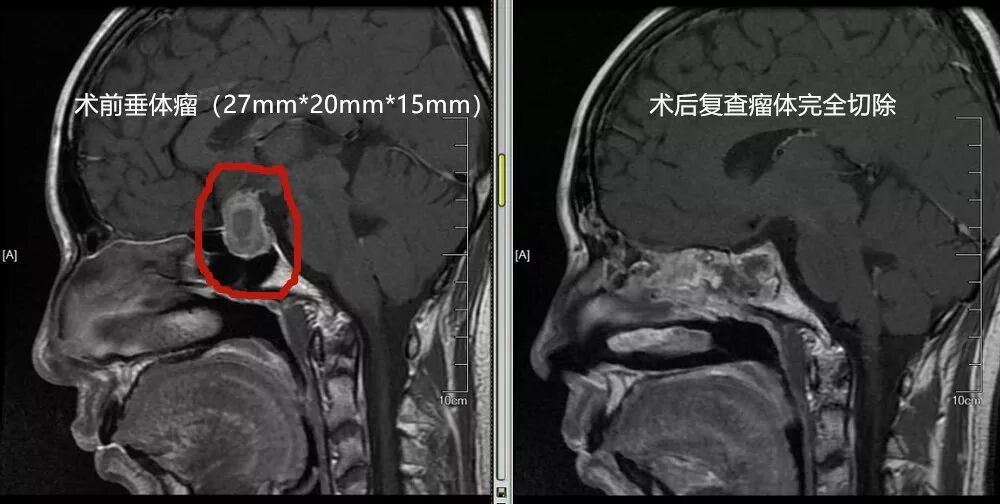

32岁的刘女士,2年前无明显诱因出现闭经、泌乳,想着自己又不是哺乳期,突然出现这种情况,刘女士决定来浏阳市人民医院看看。经我院多学科诊治,考虑垂体瘤,当时瘤体较小,刘女士在接受药物治疗后,月经正常,泌乳症状消失。今年7月份,刘女士发现自己视力明显下降,想起我院神经外科医师的叮嘱,垂体瘤进一步增大将鞍膈顶起或穿破鞍膈向鞍上生长,可压迫视交叉神经,而引起视力下降及视野改变。于是,赶紧来我院复查,发现垂体瘤已有鹌鹑蛋大小,并有神经压迫表现。我院神经外科易征主任医师看过片子,仔细询问了病史及详细查体后,告诉刘女士:泌乳、视力下降的“元凶”就是颅内这颗肿瘤,学名“垂体瘤”,也是引起刘女士泌乳素分泌增高,导致泌乳,压迫视神经,导致视力下降的“元凶”。‍

易征主任正在手术

医生建议刘女士通过手术摘除垂体瘤,可刘女士有所顾虑,想着自己这么年轻,做开颅手术需要从头皮划个大切口,把脑壳打开,想想都后怕。易主任告诉她,现在神经外科手术已进入“微创时代”,很多传统的开颅手术方式已经被替代。就像垂体瘤,经人体自然腔道,仅用两根神奇的“魔术棒”就能切除颅内肿瘤,不遗留体表切口疤痕。听到这,刘女士打消了顾虑,立马同意手术,手术如期进行,术中仅用半小时就顺利切下了肿瘤,术后一周刘女士顺利康复出院,泌乳素水平正常,视力改善。